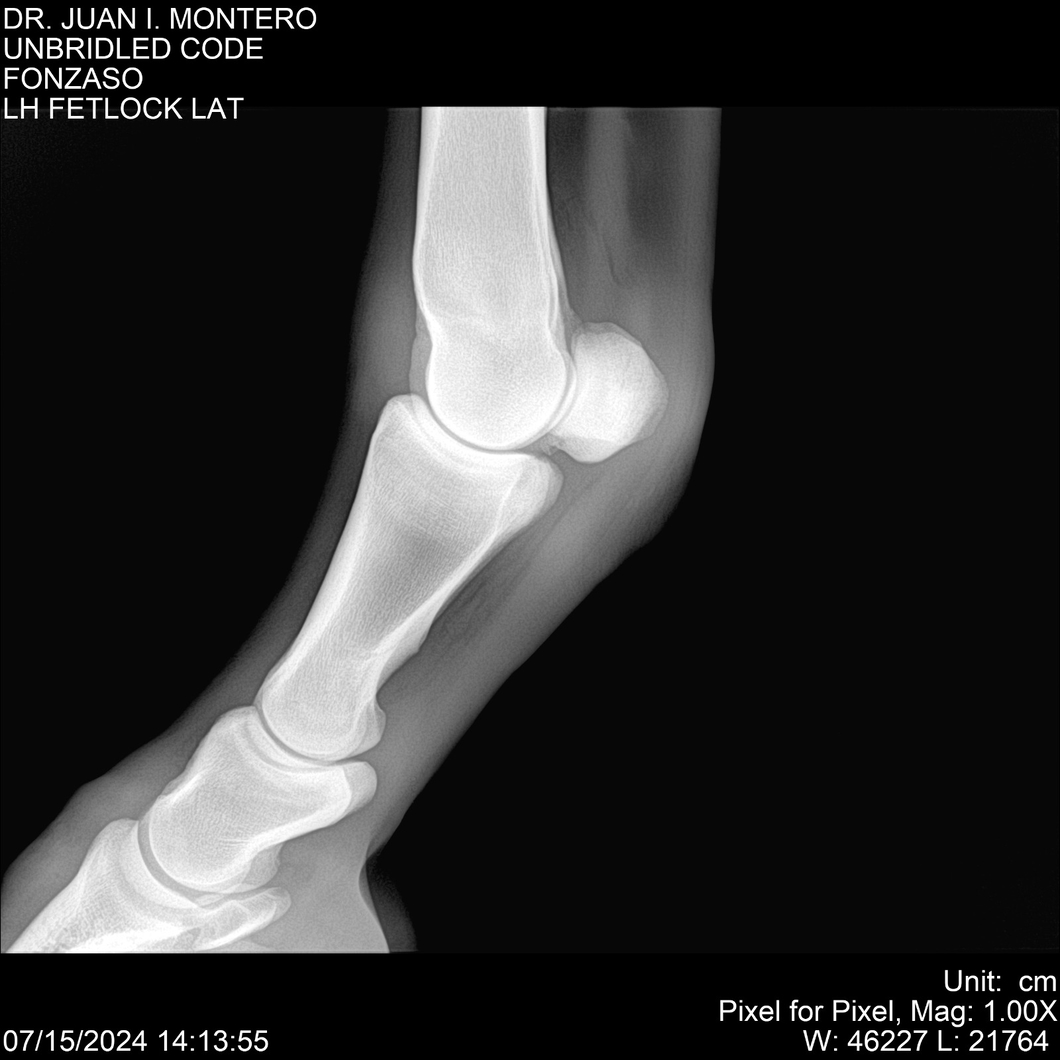

• Empresa: Abelenda N. R., Walter Hugo